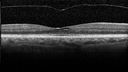

Non-central vitreomacular traction

non-central-VMT_28229.jpg

2 files, last one added on Apr 06, 2019

Album viewed 378 times